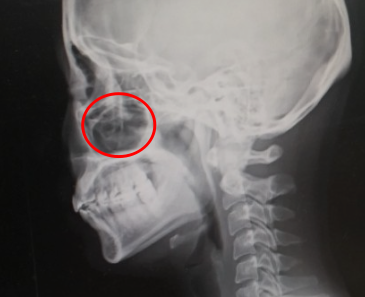

비염을 겪게 되면 보통 코가 막힌다. 심할경우 코로는 숨을 쉴 수도 없을뿐더러 위 그림처럼 비염으로 코 안쪽이 꽉 차게 되면 압력이 높아지면서 눈과의 경계 쪽을 압박해서 통증을 느낄 수 있게 된다. ( 이비인후과 선생님이 친절하게 설명해 주셨음 )

위 사진의 빨간색원이 입과, 눈과, 코의 경계를 이루는 빈 공간이다. 이 빈 공간을 비염, 치아 혹은 안압이 높아 지면서 저 부분을 압박하게 되면 상당한 통증이 발생하게 된다. 그래서 안과, 치과 등 병원에서 신경을 많이 쓰는 거라고 한다.